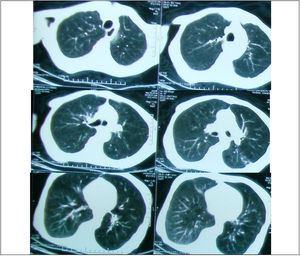

Regarding the regional distribution of abnormalities, reticular pattern and HC were the most common in the lower lung zones (Figs. 1 and 2).

Axial HRCT images at level 3 and 4 in a 38 year-old female show mixed reticular and GGO patterns as septal thickening in lung bases and limited patchy areas of GGO. This patient had FVC 61% of predicted value (mild restriction pulmonary impairment). A predominant reticular pattern and a coarseness grade of 3 were assigned.